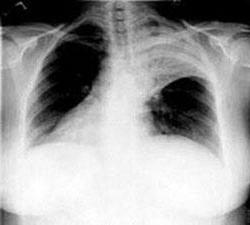

Чтобы правильно поставить диагноз доктор направит пациента на сдачу анализов, рентген. Сделает посев мокроты с целью выявления возбудителя. Потому что если пневмония вирусной этиологии то антибиотики не помогут, а только усугубят положение. С другой стороны, вирусные препараты действенны только в первые дни обнаружения симптомов, а если ситуация ухудшается, то придётся принимать антибиотики. Поэтому определение возбудителя крайне важно для правильного и эффективного лечения заболевания.

В половине случаев инфицирования пневмонией первопричиной является пневмококк.

Треть случаев заболевания провоцируют хламидии, легионеллы, микоплазма.

Совсем небольшой процент пневмонии, вызываемой гемофильной палочкой, золотистым стафилококком. Но есть ещё и вирусы (аденовирус, вирус гриппа, парагриппа и другие).